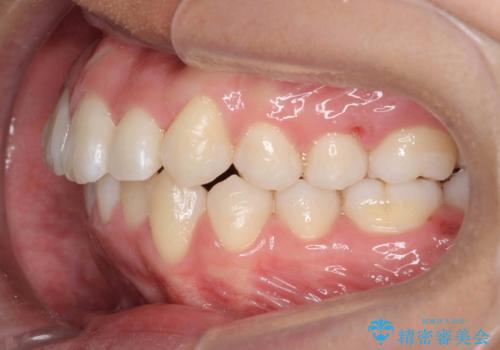

八重歯 抜かずにマウスピース矯正治療

- 八重歯を主訴に来院。

(1)口元を下げるなら、上下左右抜歯でワイヤー矯正

(2)奥歯を後ろに下げ、歯並びを拡大し、歯を少し削って抜かずにインビザライン矯正 矯正用ミニスクリュー併用 口元は下がらない

の選択肢から選んでもらいました。

目立たない装置希望とのことで、(2)を選択されました。

リファインメントもなく、1回で治療が終了しました。大変うまくいったケースです。

主治医としては、前歯の並びをもう少しこだわりたかったのですが、満足度が高く、リファインメントは希望されませんでした。

抜歯をしていないので口元は変わっていません。

八重歯も重症でなければインビザラインでも並びを歯を抜かずに整えることができます。